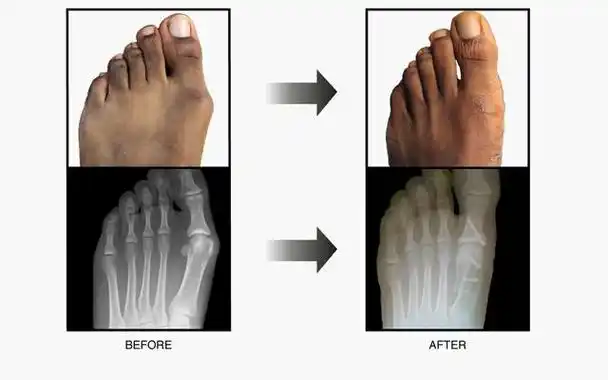

大脚骨有哪些明显症状

大脚骨的病因及临床表现